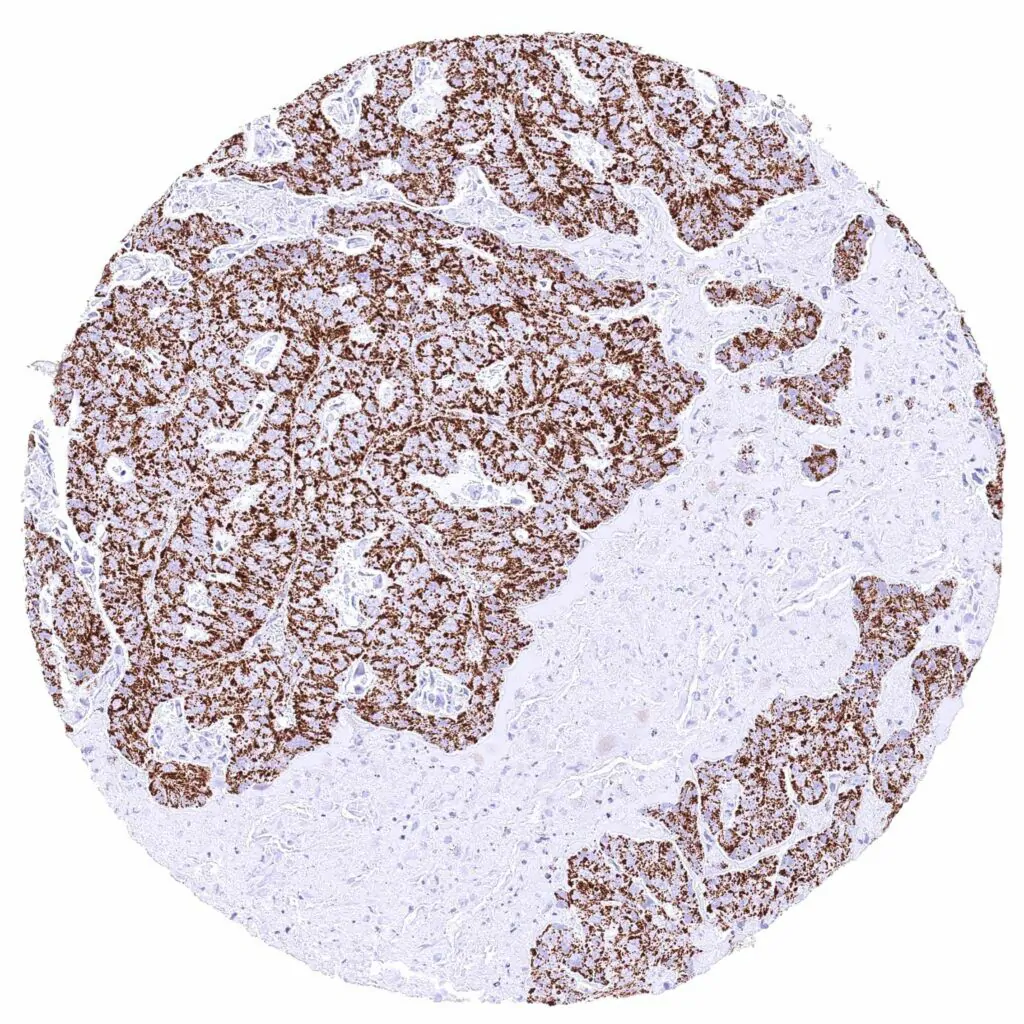

Lymph node – Diffuse large B-cell lymphoma with intense cytoplasmic ATP5J positivity of all tumor cells.